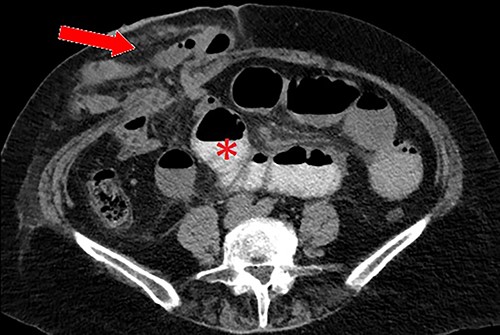

We present a 71-year-old female admitted to a tertiary hospital for an elective repair of a parastomal hernia (loop ileostomy) for recurrent obstructive symptoms. Her background history was only significant for a severe long-standing colitis which necessitated defunctioning ileostomy 3 years prior. On examination, she had a partially reducible parastomal hernia containing loops of small bowel, confirmed on preoperative computed tomography (CT) imaging (Fig. 1).

Axial CT scan with oral contrast demonstrating right-sided parastomal hernia containing small bowel loops (arrow) and proximal small bowel dilatation (asterisk).